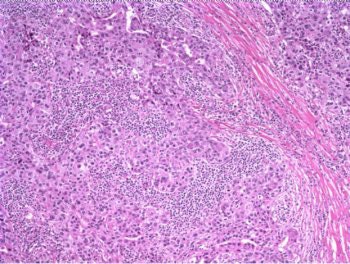

The patient underwent a lumpectomy with sentinel node biopsy. The pathology again showed extensive mitoses consistent with grade III invasive ductal carcinoma. Figure 4 (below) shows a representative microscopic section of the mass 4 cm from the nipple at a magnification factor of 100x. Figure 5 is the same area magnified 400x. Figure 6 shows a representative microscopic section from the other mass, which was 3 cm from the nipple magnified 100x. Figure 7 is magnified 400x. The tumors were estrogen receptor- and progesterone receptor-negative. Two sentinel nodes were negative.

|

Figure 4: Above, IDC right breast, 10 o'clock, 4 cm from the nipple magnified 100x. Figure 5: Below, IDC right breast, 10 o'clock, 4 cm from the nipple magnified 400x. |